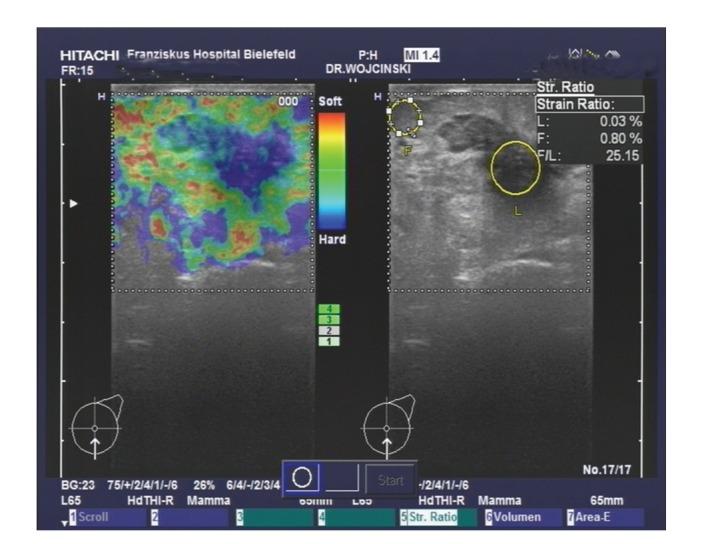

Objectives. Clinical estimation of malignant breast tumor size is critical for preoperative planning and is crucial for following up the tumor's response to the therapy in case she receives a neoadjuvant chemotharapy. Ductal carcinoma in situ (DCIS) accompanies about 25.4% of detected invasive breast cancers. The aim of this study was to examine the effect of the presence of DCIS on the accuracy of the ultrasonographic measuring malignant breast tumor size using B-mode and real time elastography. Materials and Methods. We recruited histologically confirmed breast cancer patients in a prospective observational study. Results. We recruited 50 breast cancer patients with a median age of 57.5 years. DCIS was confirmed to accompany 42% (n = 21) of the cases. Tumor size estimation using B-mode sonography (P < 0.001) as well as using real time elastography (P < 0.001). was statistically significant correlated to the actual tumor size. Presence of DCIS in 42% of our recruited patients affected the tumor size estimation using both methods thus losing the correlation between both estimations (P = 0.794). Conclusion. This study shows that the presence of DCIS significantly affects the accuracy of measuring the sizes of malignant breast tumors when using either B-mode ultrasonography or real time elastography.

https://cdn.ncbi.nlm.nih.gov/pmc/blobs/e6ac/3440853/622a85ff49e9/IJBC2012-376032.001.jpg